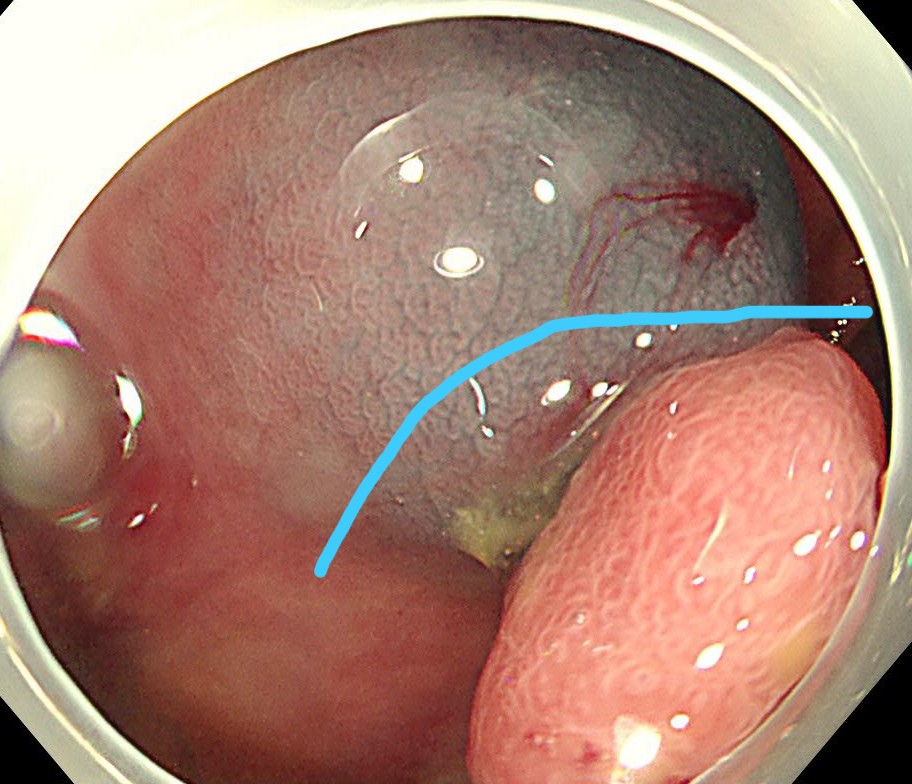

中年女性、下血にて来院。大腸内視鏡をしますと、直腸に15mm大のポリープを認めます。NBI(狭帯域光観察)では構造異形は乏しく、良性ポリープと診断しましたが、下血原因と考え、型のごとく内視鏡切除(EMR)しました。

病理診断にて直腸のSSA/P (sessile serrated adenoma/polyp 鋸歯状腺腫) と診断されました。大腸の鋸歯状腺腫はよくみられる病変ですが、右側結腸に多く、直腸は過形成性ポリープがほとんどで、直腸SSL (鋸歯状病変)は比較的まれです。またその多くが平坦な病変であるため、上記のようなⅠ型のポリープ形状は珍しい病変と思われます。最近の研究結果で直腸の隆起型のSSA/Pはがん化率が高いとする報告も散見され、注意を要する病変と思われます。